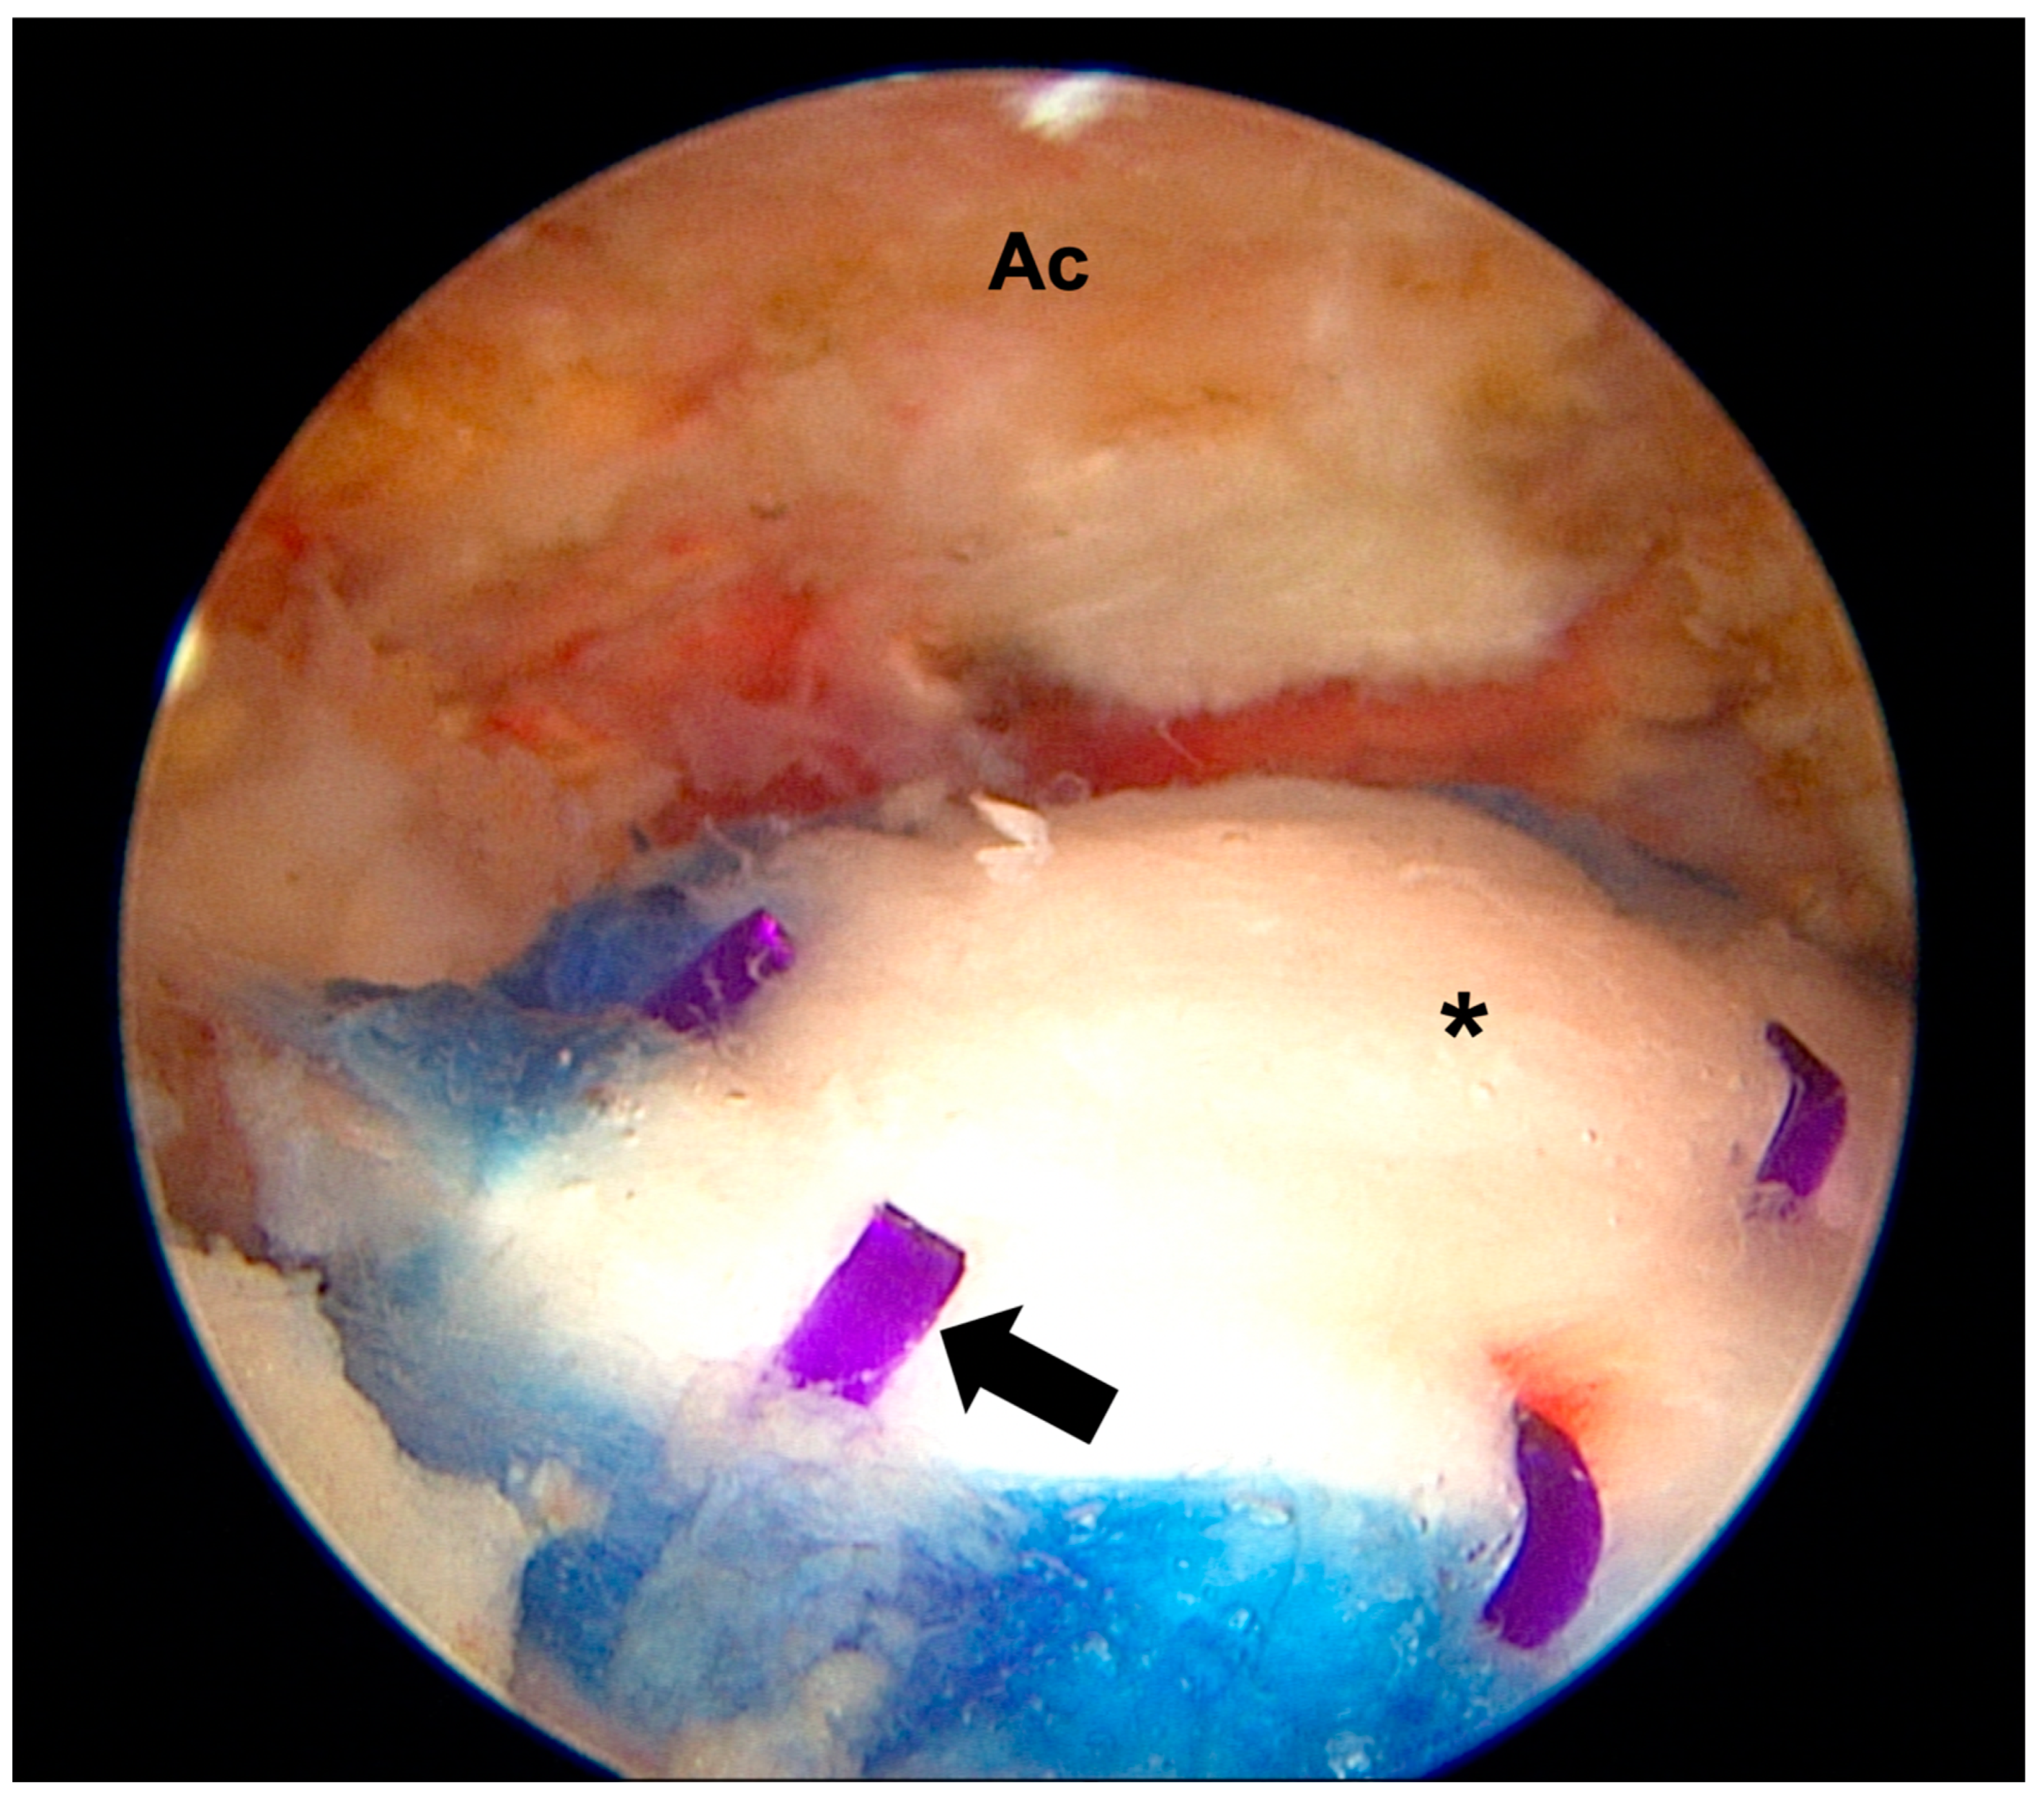

- Ruiz Ibán, M.Á.; García, N.M.; Moros, M.S.; Diaz, H.J.; Hernando, S.A.; Ruiz, D.R.; Vaquero, C.C.; Rosas, O.M.L.; Del Monte, B.G.; Ávila, L.J.L. Augmentation of a Transosseous-Equivalent Repair in Posterosuperior Nonacute Rotator Cuff Tears with a Bioinductive Collagen Implant Decreases the Retear Rate at One Year: A Randomized Controlled Trial. Arthrosc. J. Arthrosc. Relat. Surg. 2023, 40, 1760–1773. [Google Scholar] [CrossRef] [PubMed]

- Camacho-Chacon, J.A.; Cuenca-Espierrez, J.; Roda-Rojo, V.; Martin-Martinez, A.; Calderon-Meza, J.M.; Alvarez-Alegret, R.; Martin-Hernandez, C. Bioinductive collagen implants facilitate tendon regeneration in rotator cuff tears. J. Exp. Orthop. 2022, 9, 53. [Google Scholar] [CrossRef]

- Bokor, D.J.; Sonnabend, D.; Deady, L.; Cass, B.; Young, A.; Van Kampen, C.; Arnoczky, S. Evidence of healing of partial-thickness rotator cuff tears following arthroscopic augmentation with a collagen implant: A 2-year MRI follow-up. Muscles Ligaments Tendons J. 2016, 6, 16–25. [Google Scholar] [CrossRef]

- Bushnell, B.D.; Connor, P.M.; Harris, H.W.; Ho, C.P.; Trenhaile, S.W.; Abrams, J.S. Two-year outcomes with a bioinductive collagen implant used in augmentation of arthroscopic repair of full-thickness rotator cuff tears: Final results of a prospective multicenter study. J. Shoulder Elb. Surg. 2022, 31, 2532–2541. [Google Scholar] [CrossRef]